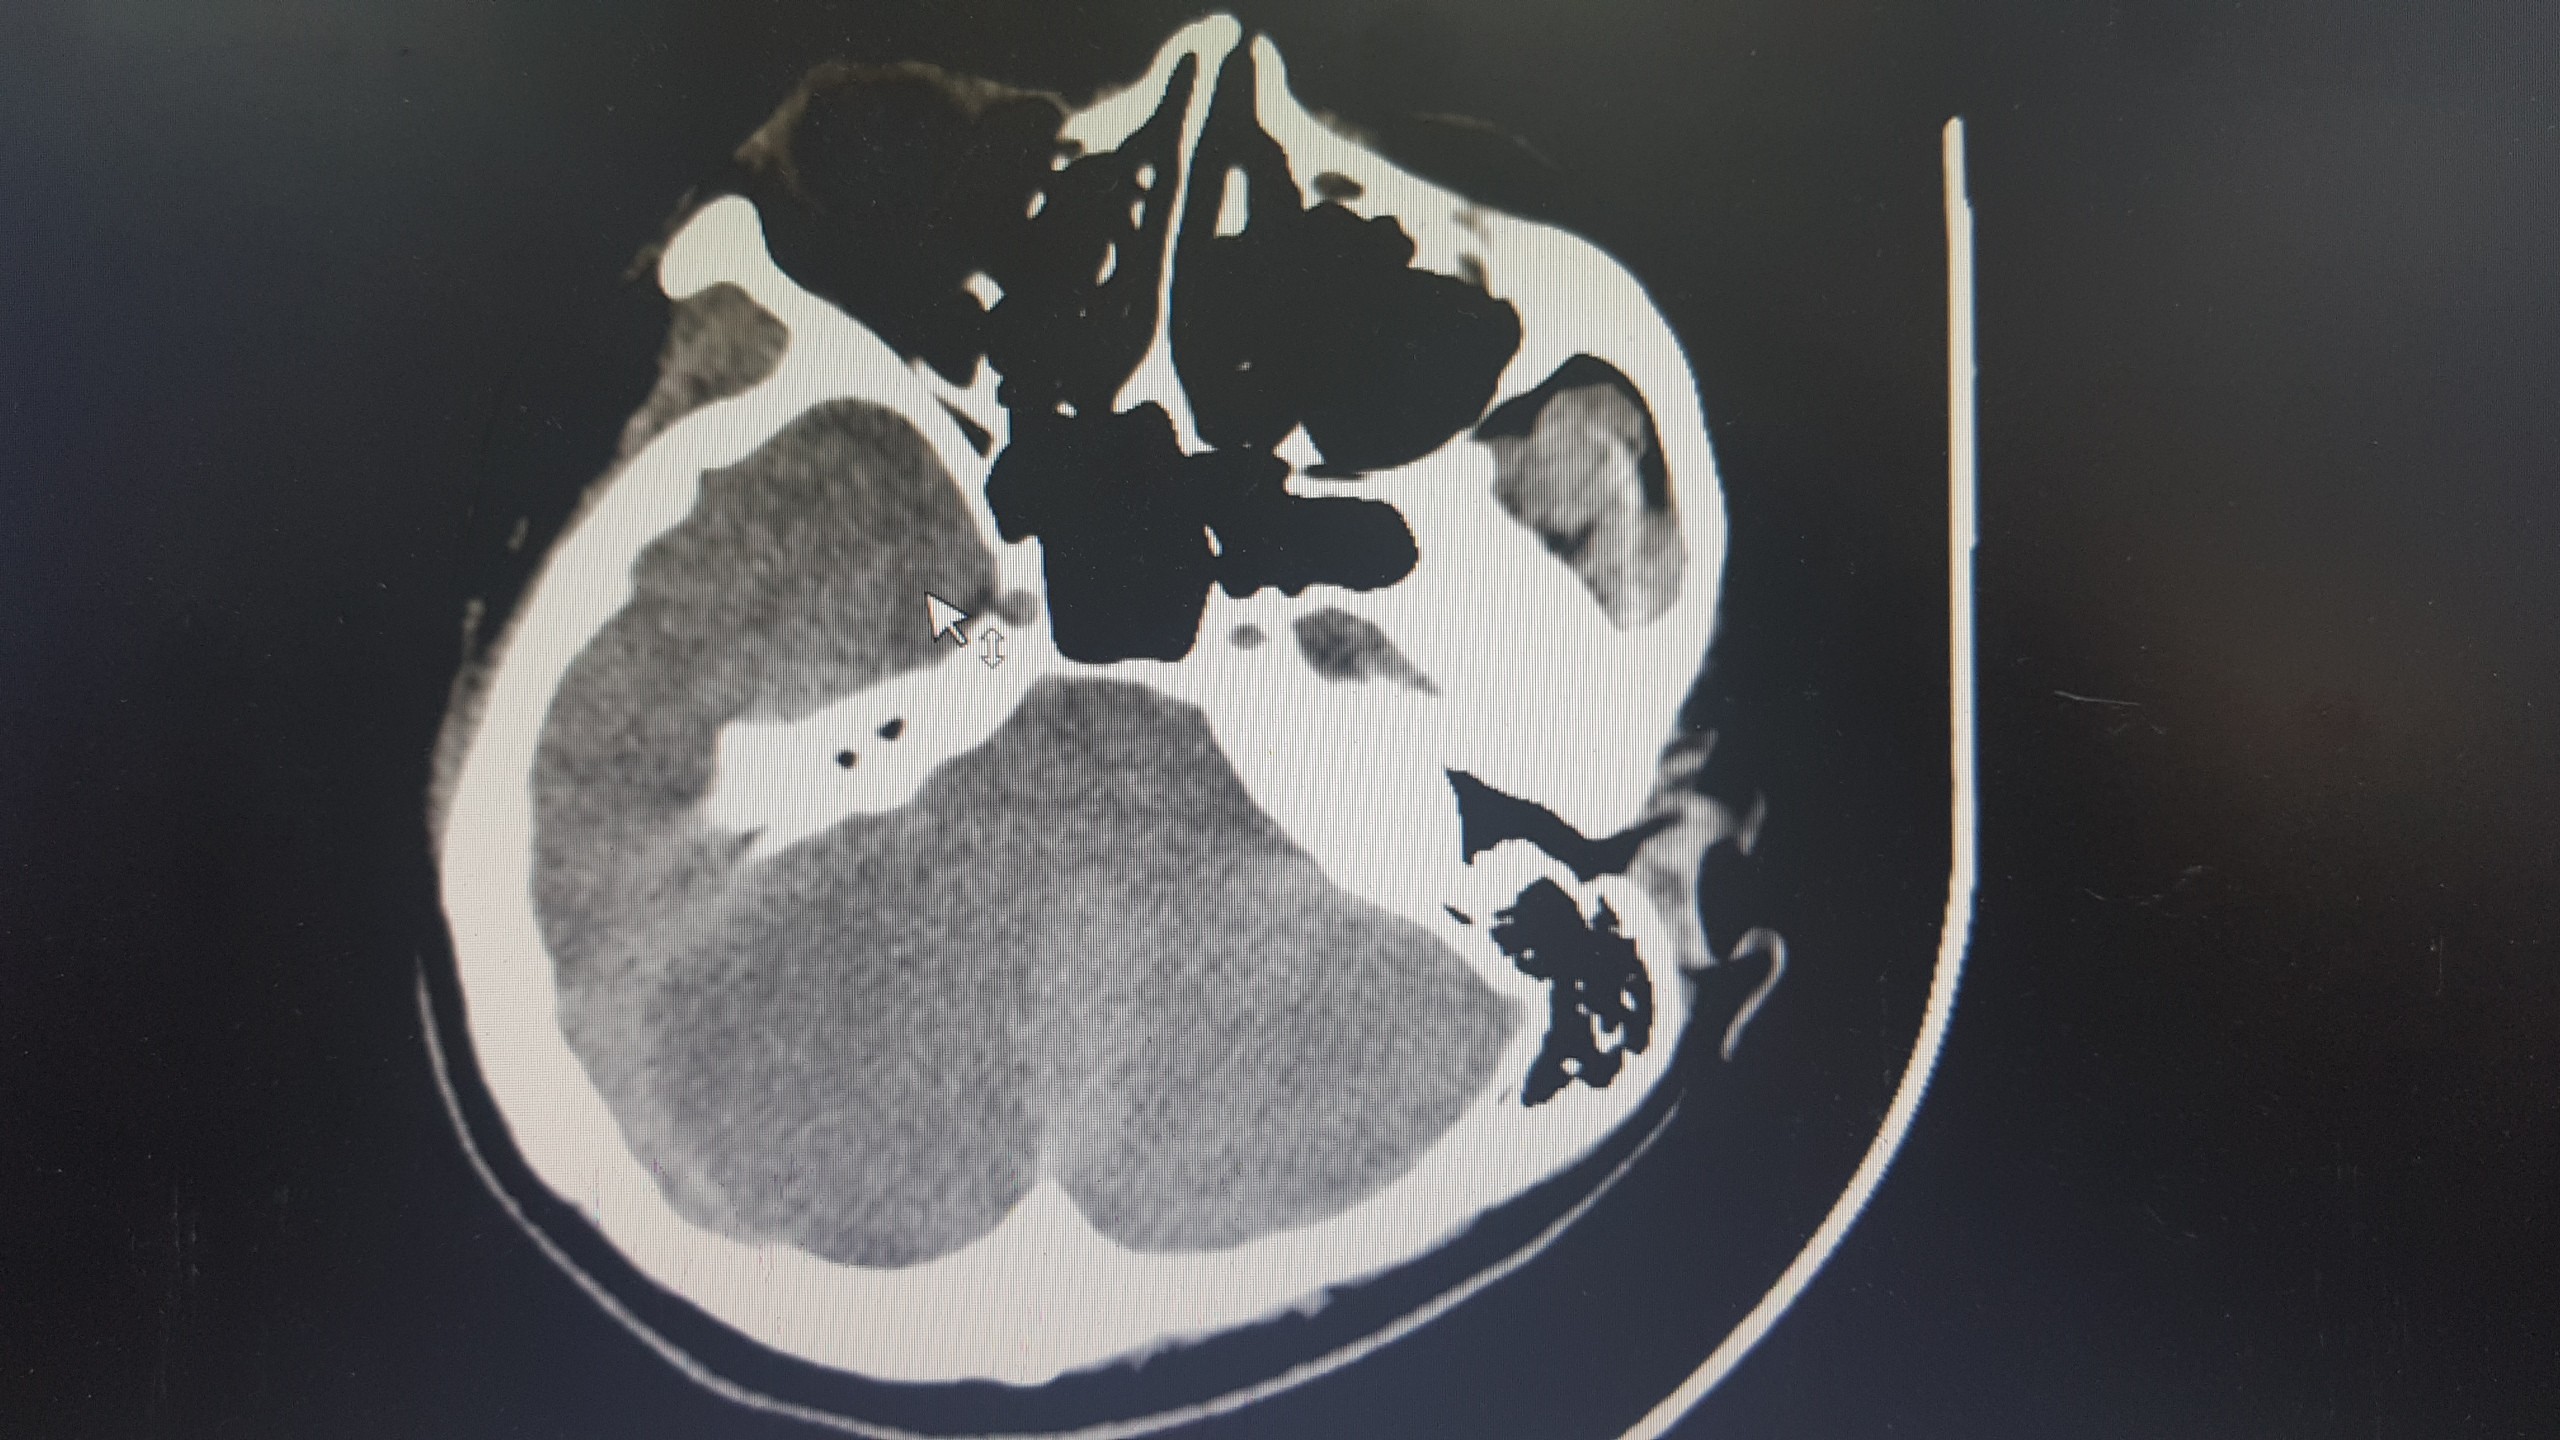

TS.BS. Nguyễn Trung Nguyên, Giám đốc Trung tâm Chống độc, Bệnh viện Bạch Mai cho biết: Bệnh nhân đang trong tình trạng rất nguy kịch do tổn thương và suy nhiều cơ quan, trong đó nặng nhất là tổn thương não lan tỏa tại tất cả các vị trí. Trường hợp của bệnh nhân gần giống như ca đột quỵ não nhưng nặng hơn rất nhiều. Nếu đột quỵ não chỉ gây tổn thương nhỏ ở một số vị trí thì ở trường hợp này là tổn thương gần như toàn bộ não. Ngoài ra, bệnh nhân còn bị tổn thương và suy tim nặng, suy thận, tổn thương gan. Tiên lượng điều trị và hồi phục của bệnh nhân là vô cùng dè dặt.

Ảnh chụp não bị tổn thương của bệnh nhân